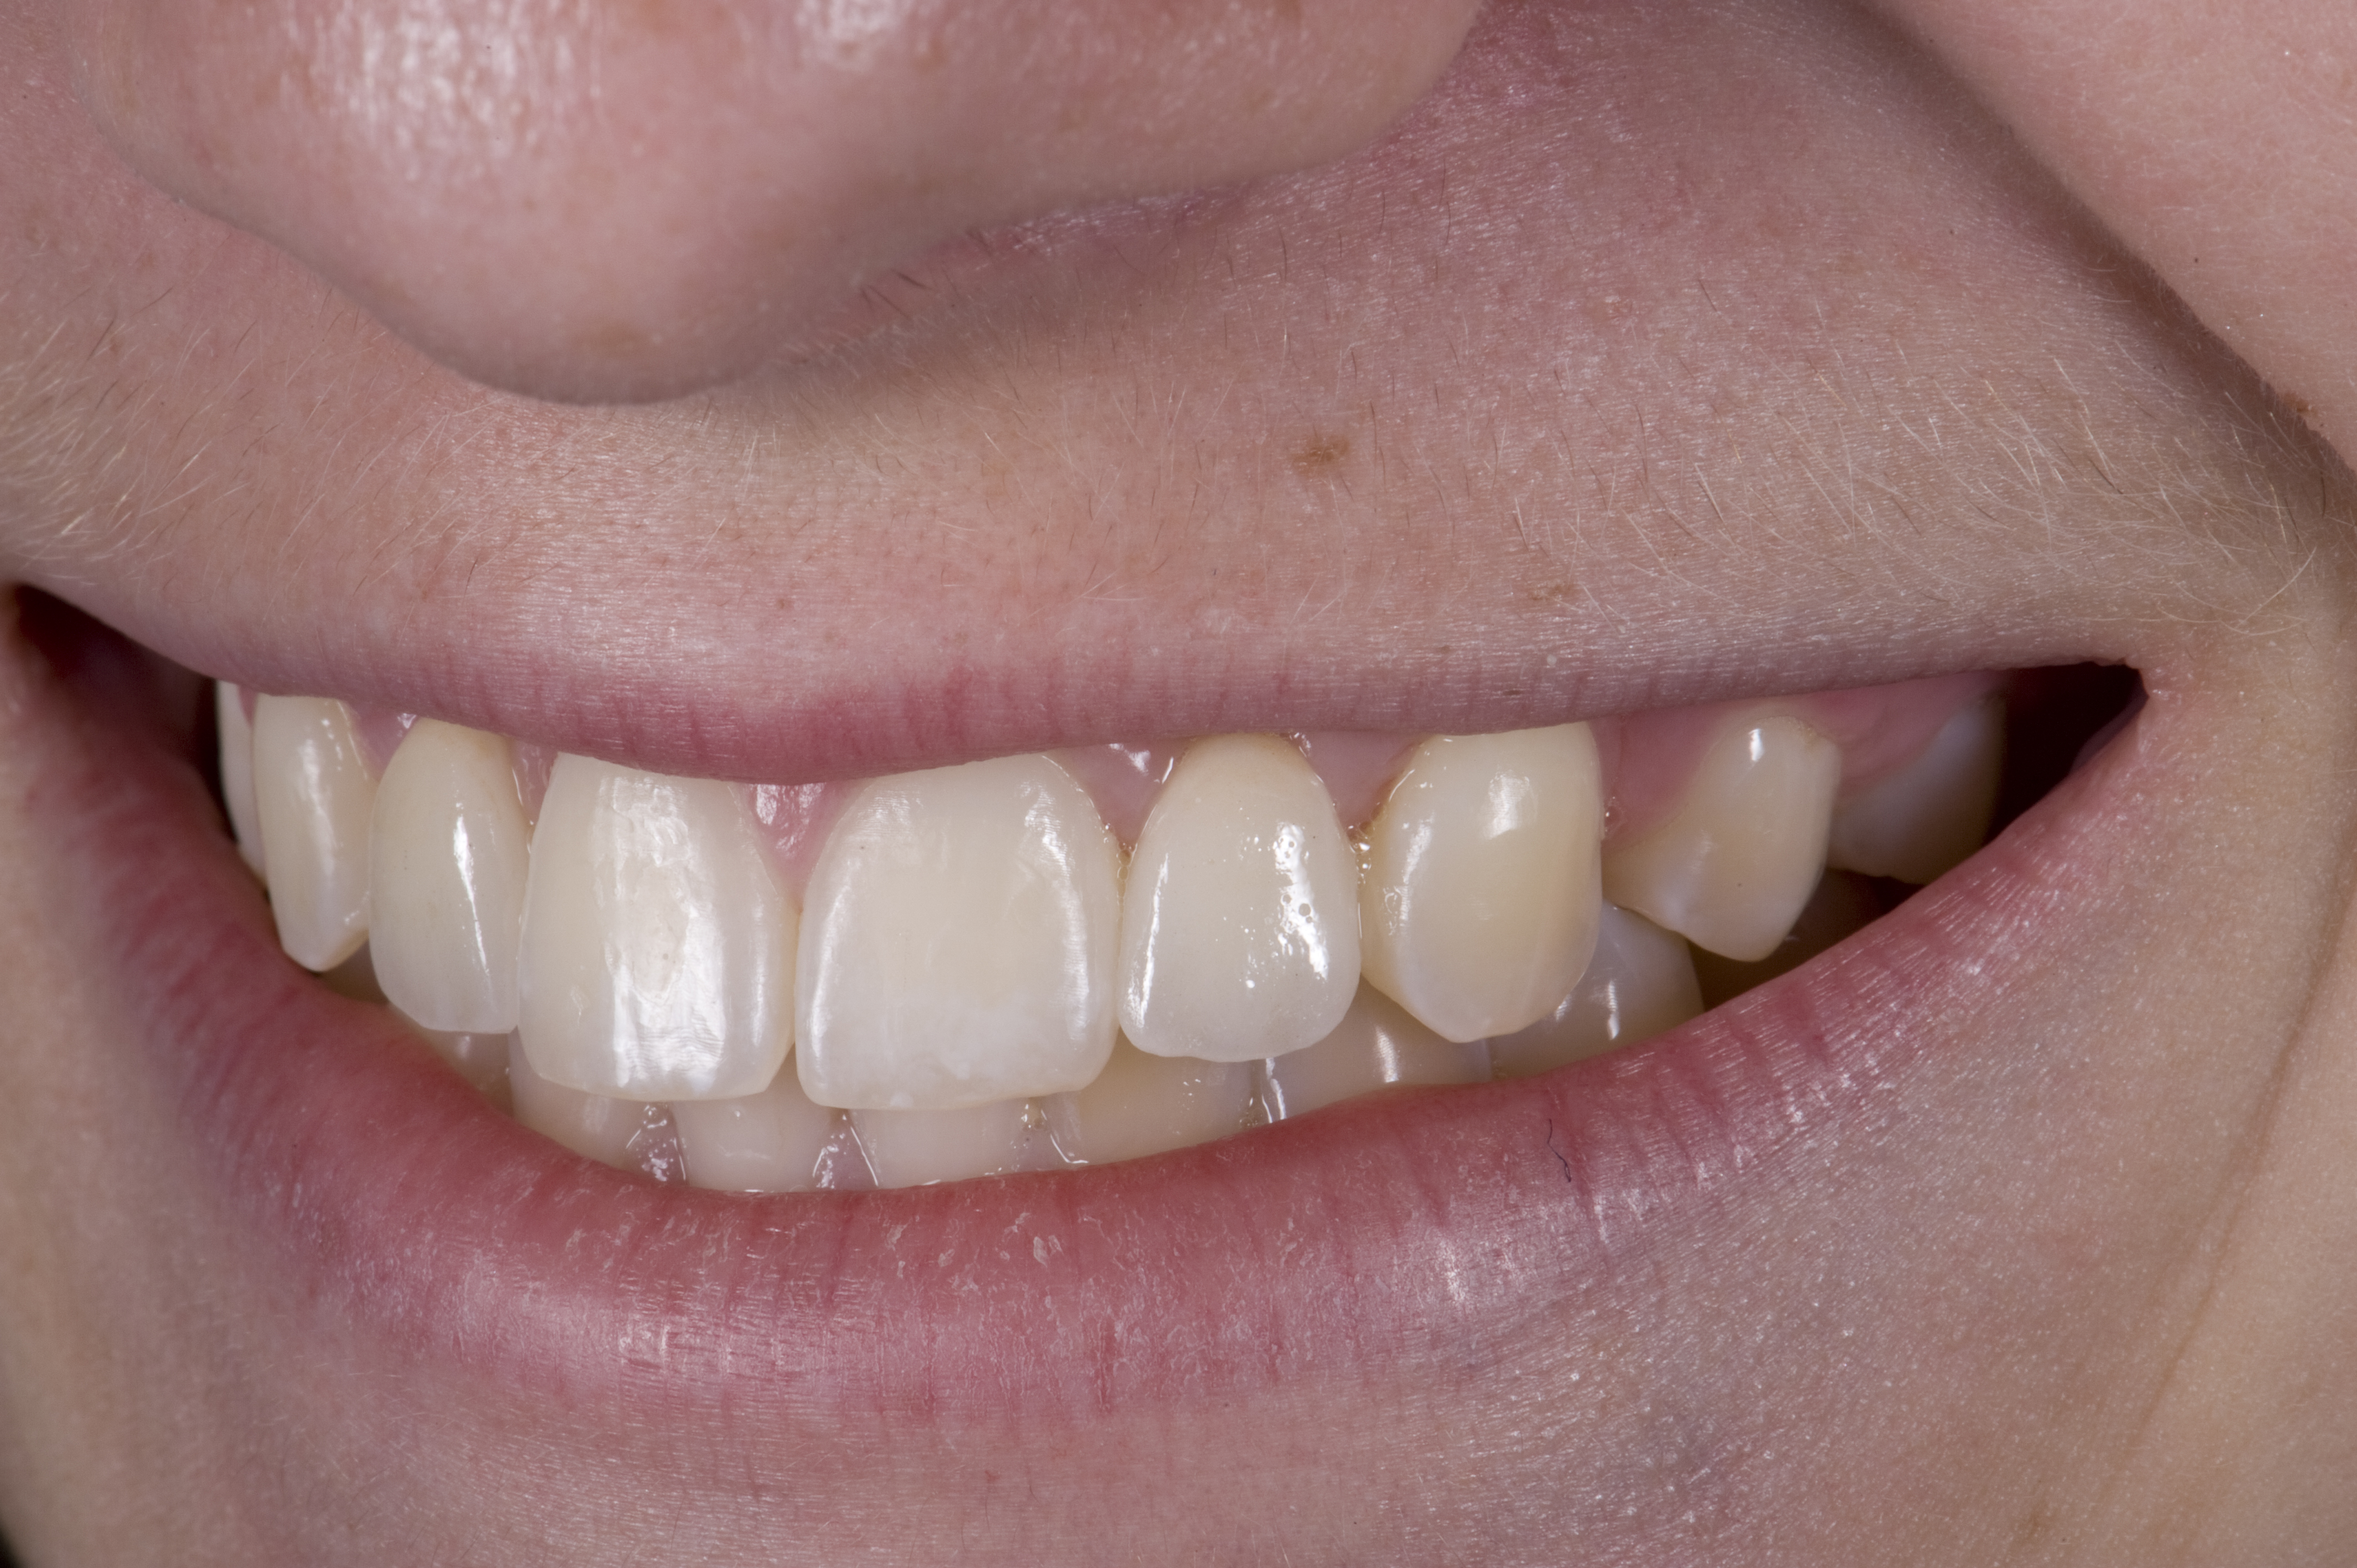

(12.) 15-year-old girl after orthodontic therapy idealized maxillary lateral incisor spaces.

Figure 12